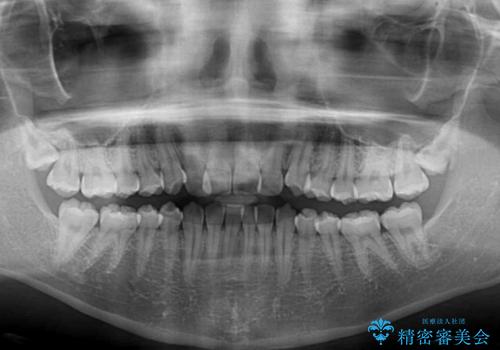

- 前歯のクロスバイトを気にして来院された患者様です。

前歯の叢生を解消するスペースを獲得するために上顎左右の親知らずを抜歯し、メタルブラケットにて矯正治療を行うこととしました。